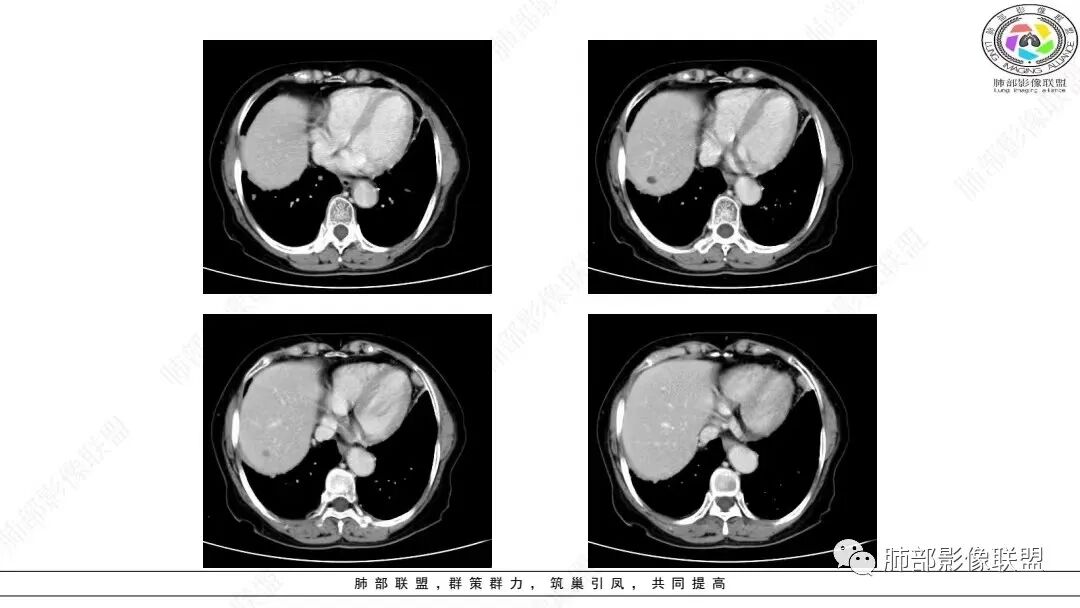

2.影像学特点:右肺上叶前段胸膜下不规则较大团块影,边界清楚欠光整,浅分叶,肺血管支气管出入,边缘膨隆胸膜凹陷具有一定张力,未见典型粗短毛刺,部分围以边界清楚的磨玻璃影,灶周小叶间隔增厚。块影密度不均,渐进性强化,可见砂砾样钙化,未见明显液化坏死或空洞。增强后病灶显示渐进性强化。MIP显示病灶内肺动脉穿行、并部分肺动脉受侵变细。纵隔及右锁骨上(胸廓入口)见肿大淋巴结。两肺可见多发大小不一的结节影,边界清楚,随机分布。

胸椎体溶骨性吸收破坏,突破骨皮质。腹部扫描未见肿块影。

病灶较大较光整,支气管出入,缀以边界清楚磨玻璃影,有一定张力,不均匀强化,疑及肺腺癌或者大细胞肺癌都在情理之中。双肺多发病灶,符合转移瘤特征。     注意胸椎体溶骨性吸收破坏,突破骨皮质,经验上这样的改变更支持转移而不支持淋巴类肿瘤。

病理结果给出淋巴上皮瘤样癌不算意外,但宜排除鼻咽来源导致两肺转移。本例核实病历后该患者并无鼻咽不相关病变。右肺上叶病灶更符合原发。